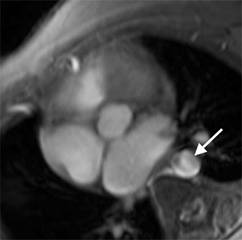

o Velocity-Encoded Cine MR Imaging For Quantification Of Collateral Circulation & Determining The Severity Of Aortic Coarctation- (Left) Oblique sagittal SE MR image show an aortic coarctation (top image). The bottom image shows how to obtain a velocity encoded image at the level of the coarctation (C) and the planes selected for velocity-encoded cine MR acquisitions for the proximal (P) and distal (D) thoracic aorta. Both planes are perpendicular to the direction of blood flow in the descending aorta. Middle images show magnitude and right images show phase images obtained from velocity-encoded acquisitions in proximal (top image) and distal (bottom image) locations of the descending aorta.